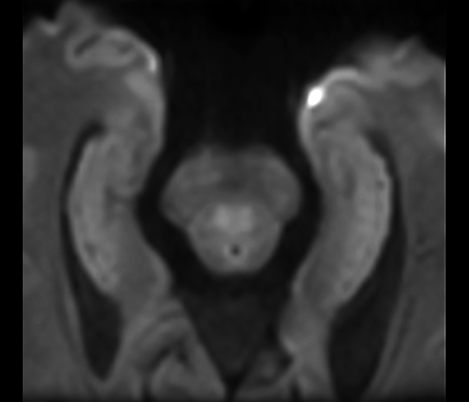

Black Blood MRI imaging of HIV patient with brain vasculitis

Black Blood imaging helped in suggesting the diagnosis and choosing the treatment.